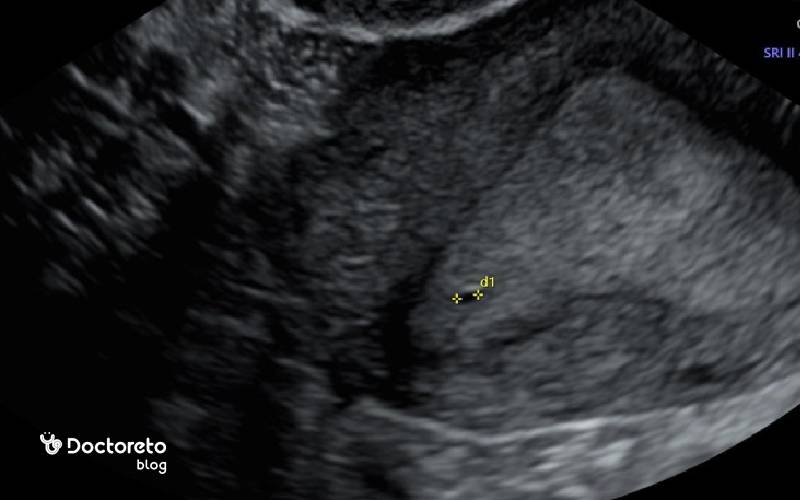

عکس سونوگرافی هفته سوم بارداری

سونوگرافی هفته سوم بارداری روش دقیقی برای تشخیص بارداری نیست.

در هفته سوم، تشخیص قطعی دشوار است چون hCG تازه شروع به افزایش می‌کند و هنوز به آستانه‌های معمول بسیاری از بی‌بی‌چک‌ها نرسیده است. آزمایش خون کمی hCG نسبت به تست ادراری حساس‌تر است و ممکن است اندکی زودتر مثبت شود، اما حتی خون نیز در این مقطع می‌تواند مرزی باشد. سونوگرافی در هفته سوم بارداری هنوز چیزی نشان نمی‌دهد. کیسه بارداری معمولاً از حوالی هفته ۴٫۵ تا ۵ دیده می‌شود. بنابراین نتیجه منفی در این هفته بارداری را رد نمی‌کند و تکرار تست بارداری در زمان مناسب اهمیت دارد.

خیر، سونوگرافی واژینال روش ایمن و کم‌خطری است و از امواج صوتی استفاده می‌کند، نه اشعه. مشکل اصلی این زمان «کمبود اطلاعات تصویری» است، نه خطر؛ چون هنوز معمولاً چیزی برای دیدن وجود ندارد. به‌طور معمول رویت کیسه بارداری از حدود هفته ۴.۵–۵ ممکن می‌شود. زمان انجام سونو را طبق نظر پزشک تنظیم کنید.

معمولاً خیر. در هفته سوم محصول بارداری میکروسکوپی است و کیسه بارداری هنوز دیده نمی‌شود. رویت کیسه معمولاً از حدود هفته ۴.۵–۵ و رویت ضربان قلب بعد از هفته ۶ امکان‌پذیر است. انجام سونو خیلی زودهنگام چیزی به تشخیص اضافه نمی‌کند و بهتر است طبق زمان‌بندی پیشنهادی پزشک انجام شود.